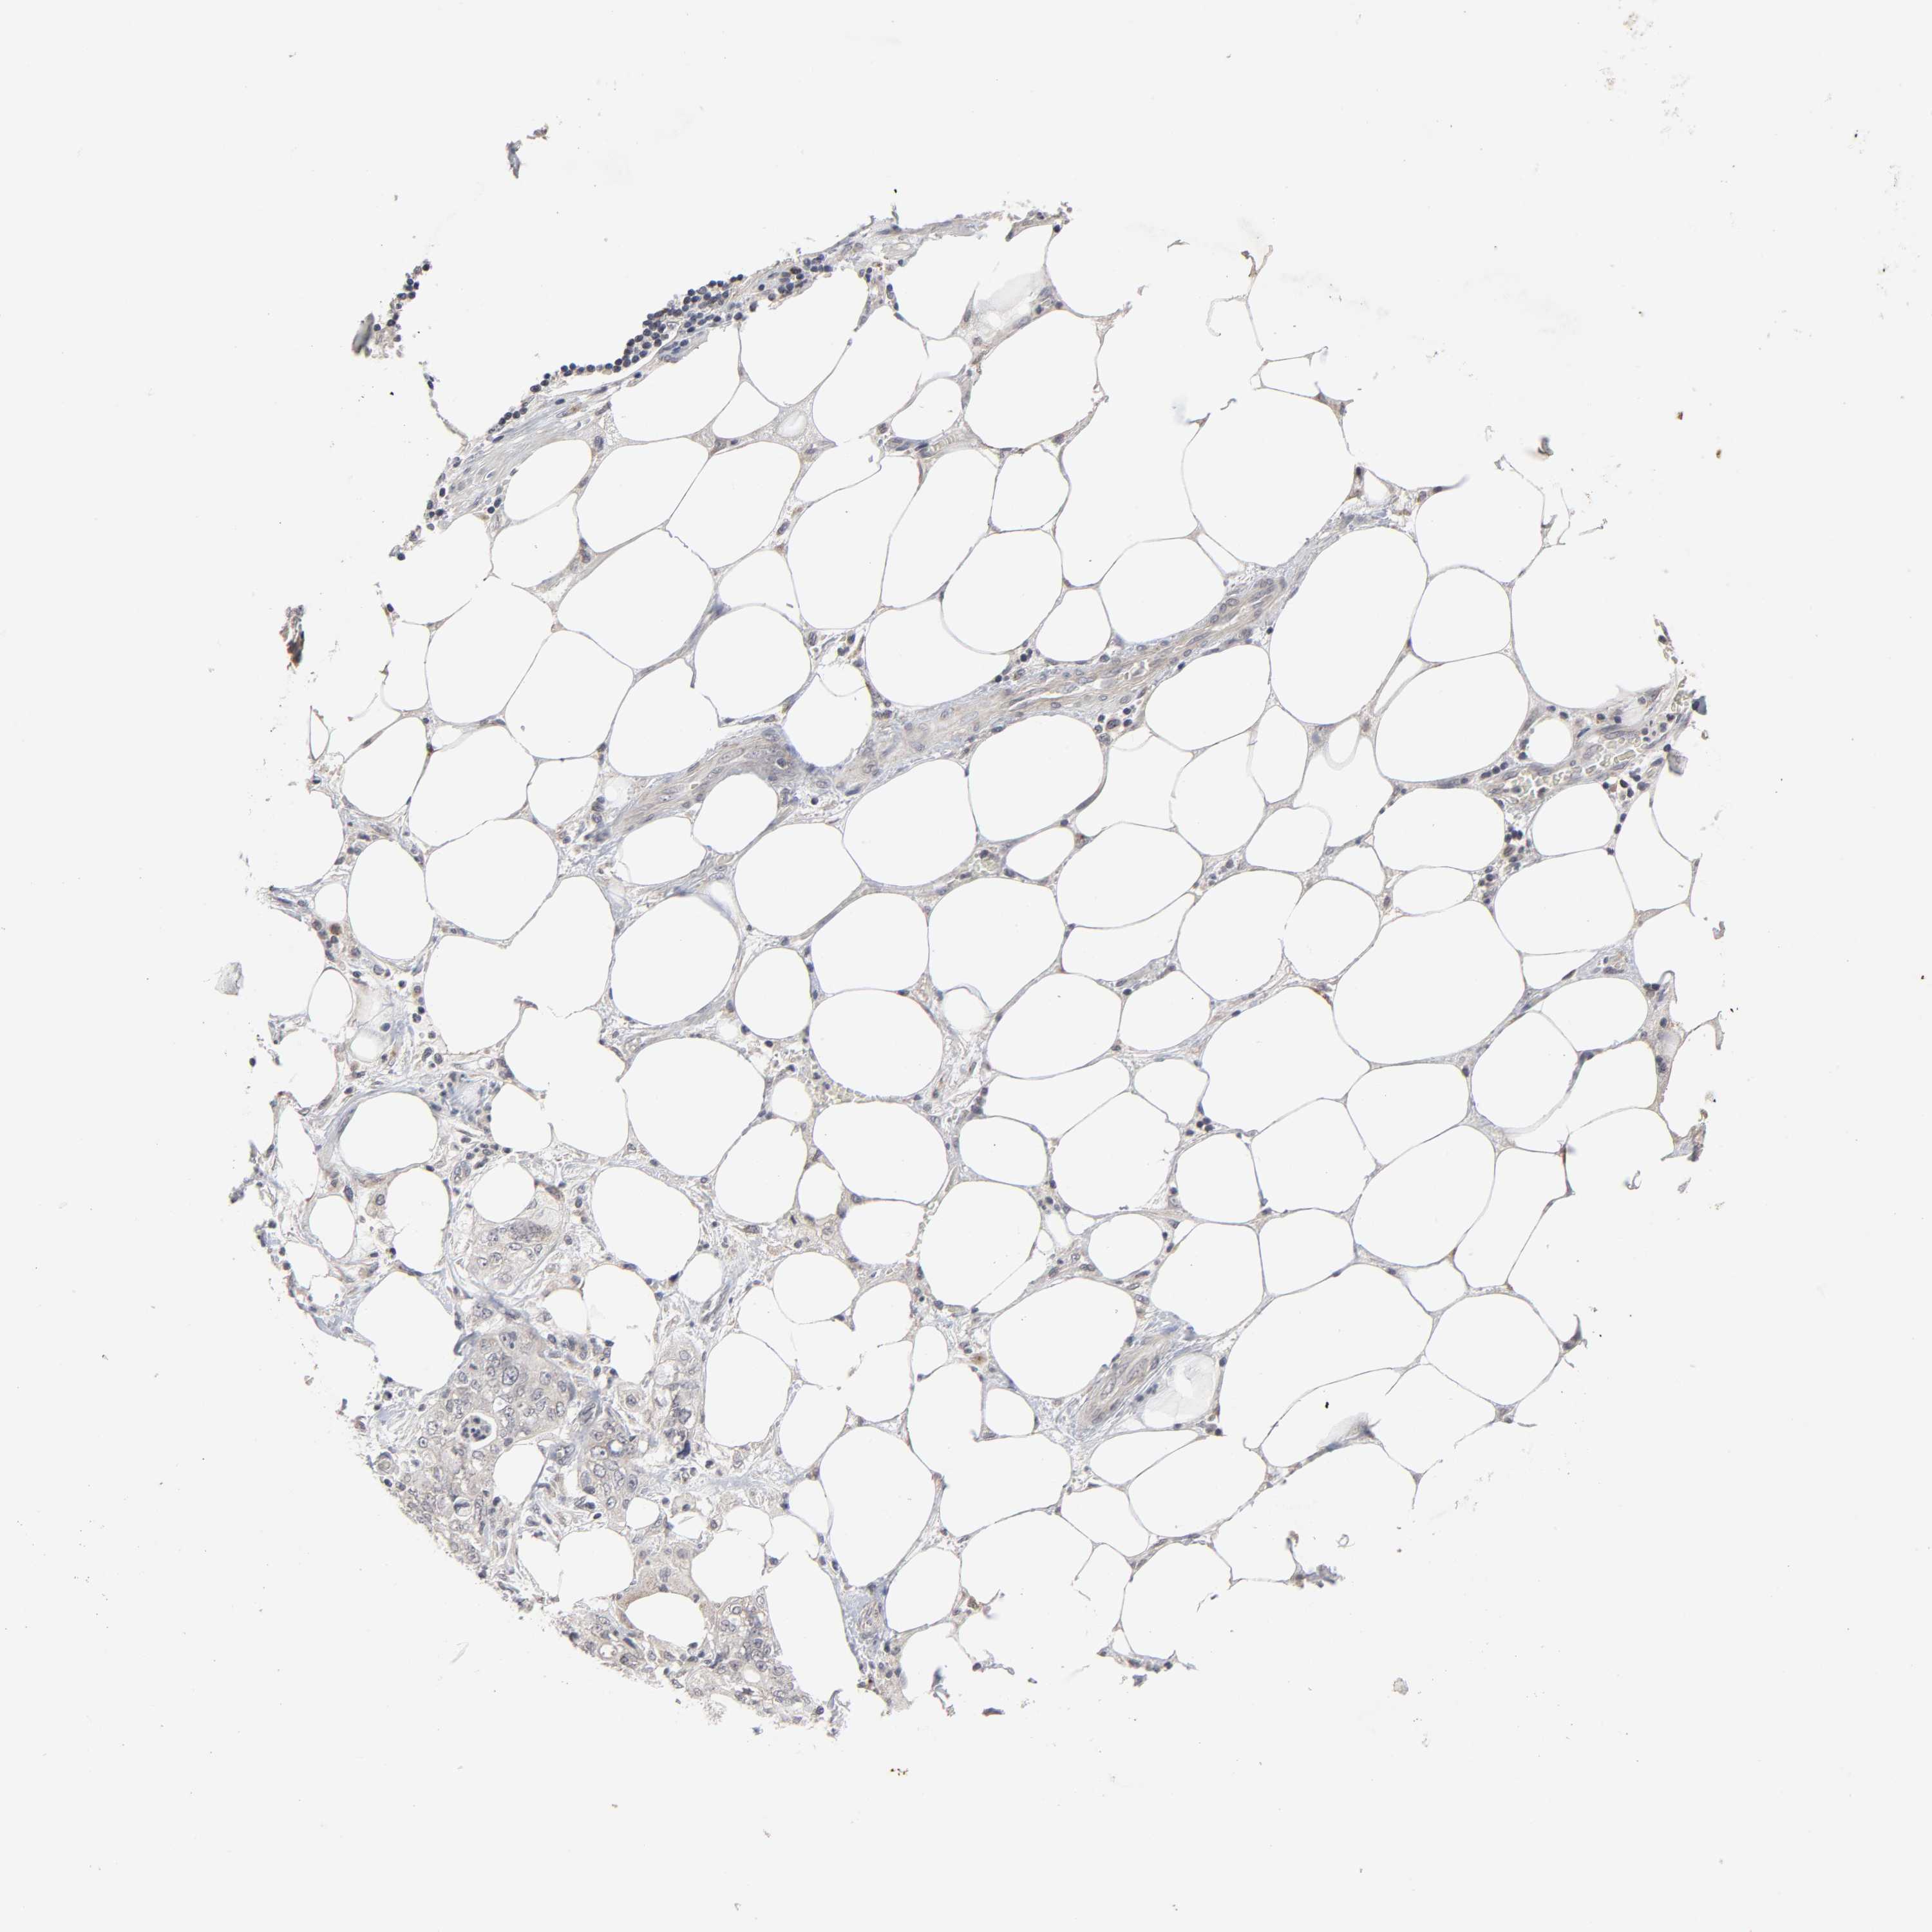

PANCREATIC CANCER - Protein expressioni

A mouse-over function shows sample information and annotation data. Click on an image to view it in a full screen mode. Samples can be filtered based on level of antibody staining by selecting one or several of the following categories: high, medium, low and not detected. The assay and annotation is described here.

Note that samples used for immunohistochemistry by the Human Protein Atlas do not correspond to samples in the TCGA dataset.

Antibody stainingi

Antibody staining in the annotated cell types in the current human tissue is reported as not detected, low, medium, or high, based on conventional immunohistochemistry profiling in selected tissues. This score is based on the combination of the staining intensity and fraction of stained cells.

Each image is clickable and will lead to virtual microscopy that enables deeper exploration of all samples and also displays staining intensity scores, fraction scores and subcellular localization as well as patient and tissue information for each sample.

Antibody HPA004171

Staining

High

Medium

Low

Not detected

Intensity

Strong

Moderate

Weak

Negative

Quantity

>75%

75%-25%

<25%

None

Location

Nuclear

Cytoplasmic/membranous

Cytoplasmic/membranous,nuclear

Adenocarcinoma, NOS

Adenocarcinoma, metastatic, NOS